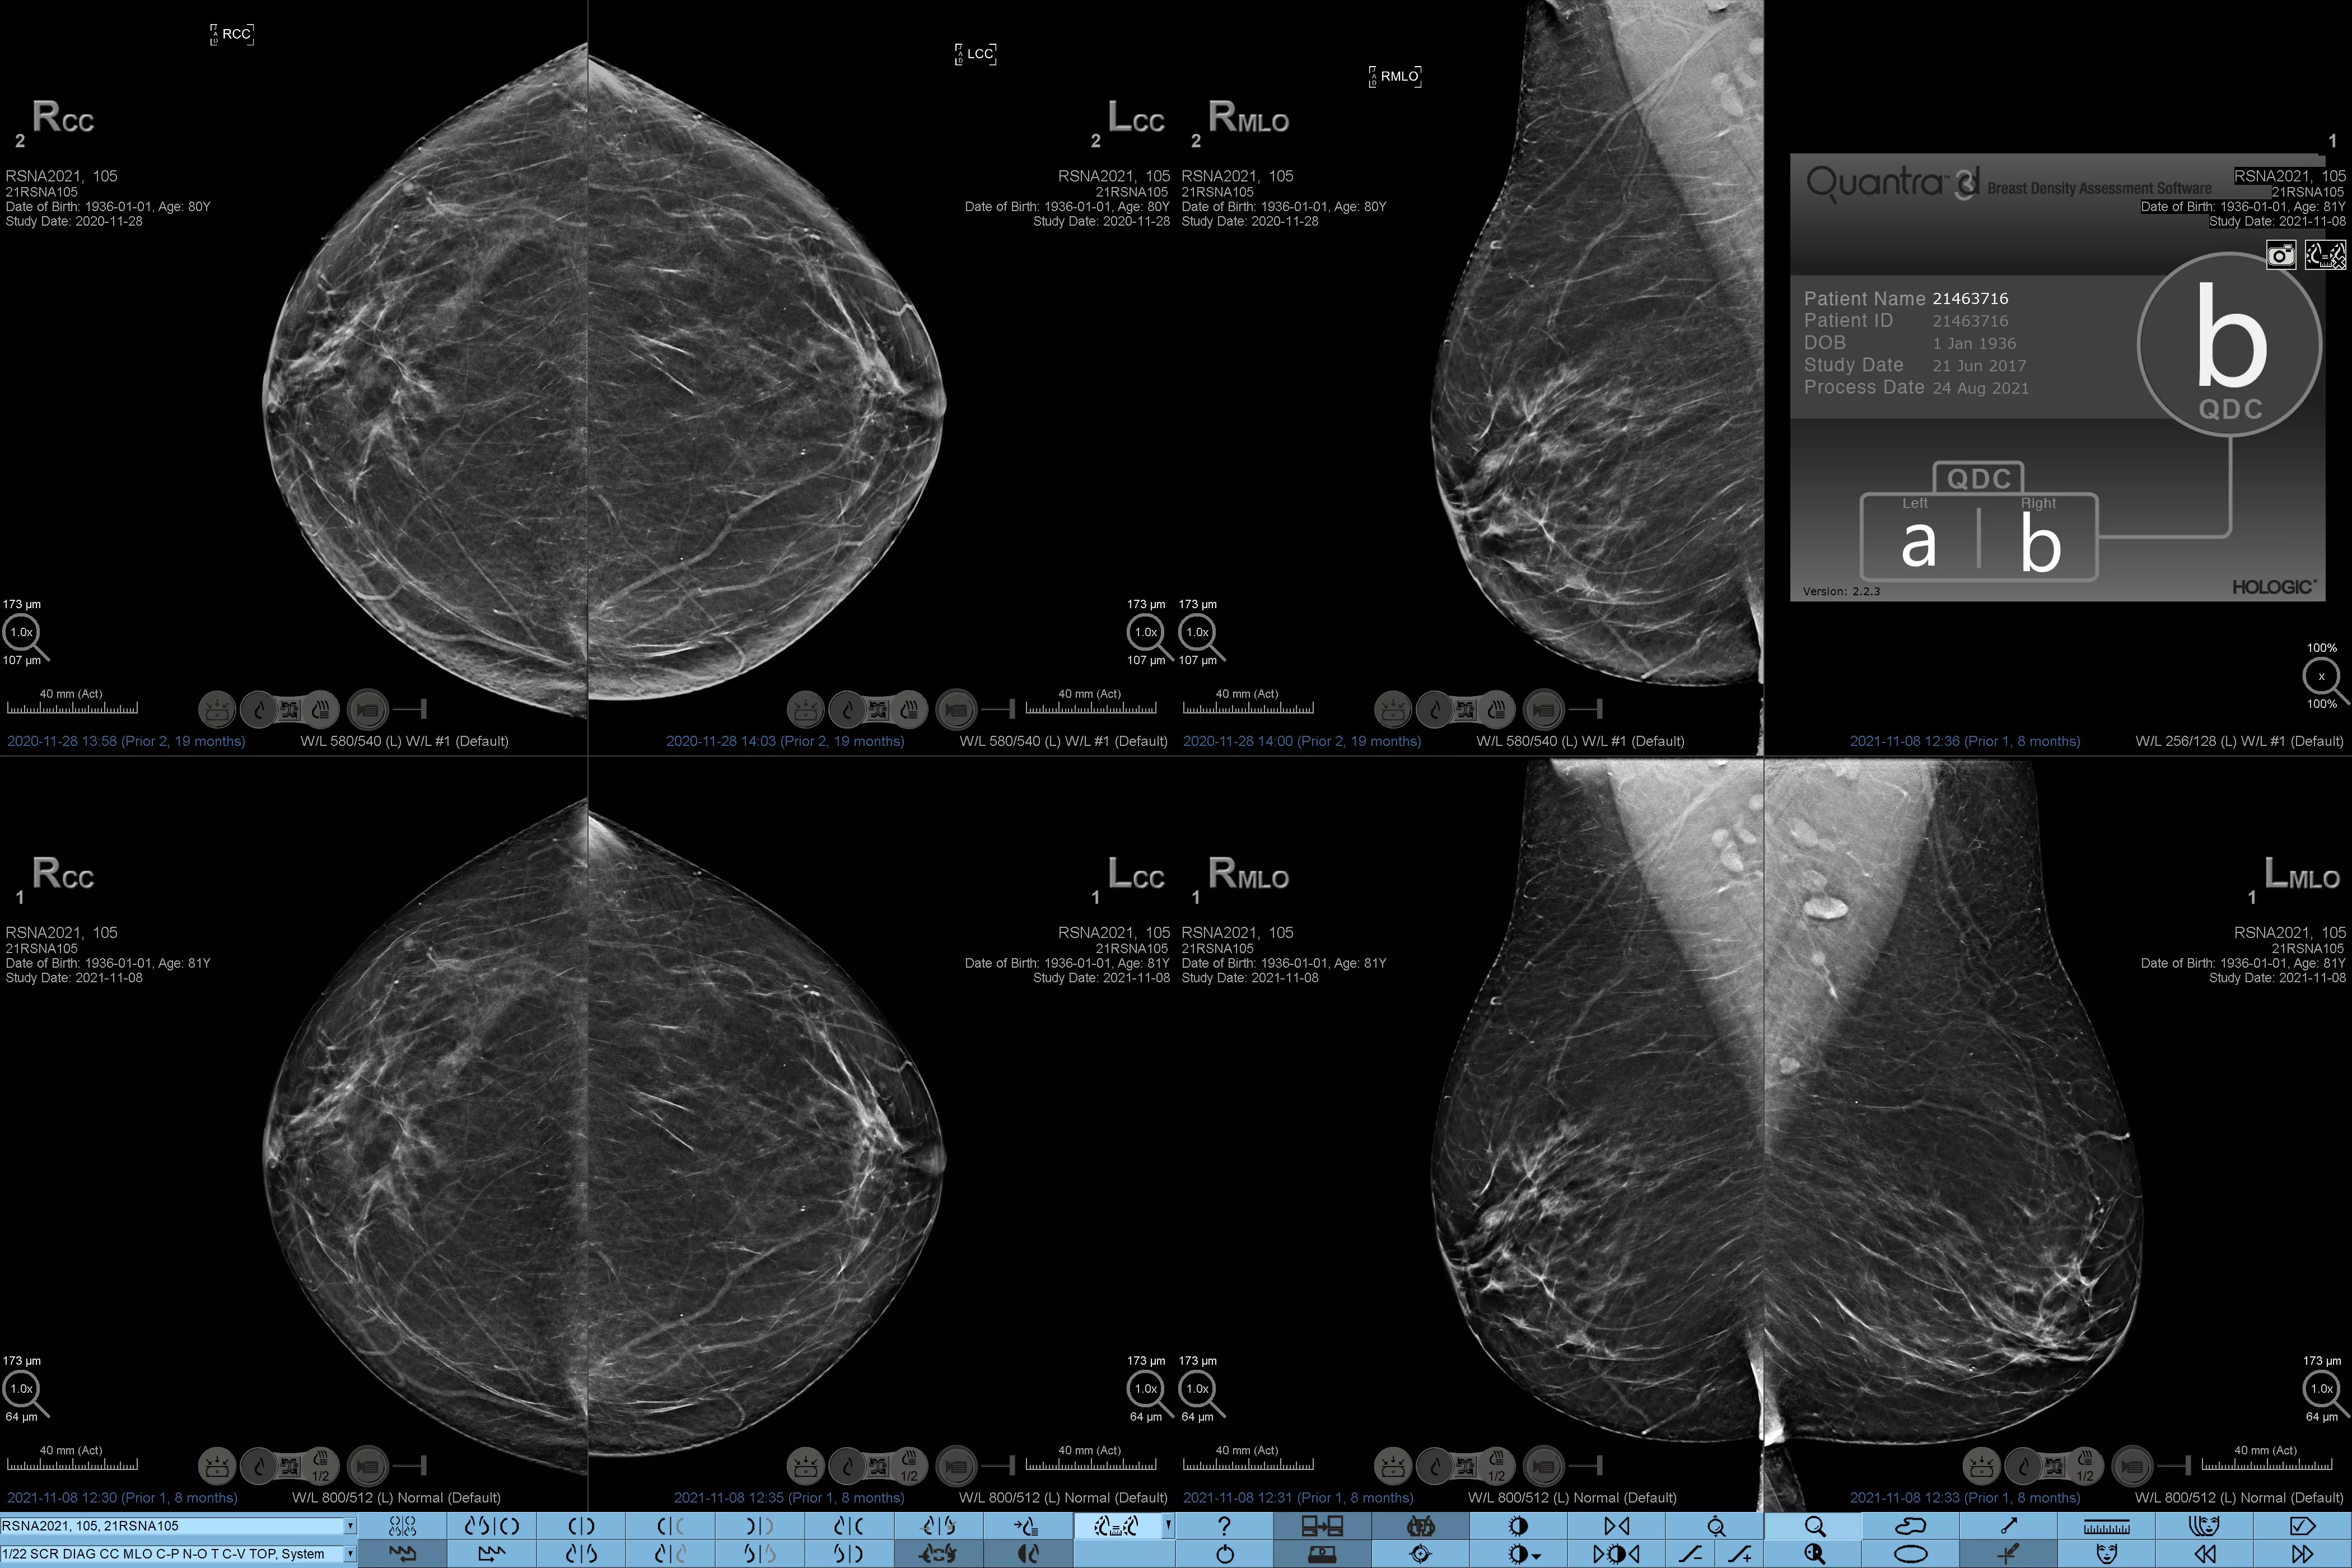

Det är känt att en hög brösttäthet ökar en kvinnas risk för bröstcancer.1 Behovet av noggrann och opartisk analys är därför kritiskt. Med hjälp av maskininlärning analyserar Quantra Technology-programvaran både 2D™- och tomosyntesbilder för fördelning och textur av parenkymal vävnad. Den kategoriserar bröst i fyra bröstkategorier utifrån sammansättning enligt riktlinje från American College of Radiology (ACR) BI-RADS Atlas 5th Edition.2

Objektiv maskininlärningsalgoritm som tilldelar en kategori för brösttäthet baserat på analys av bröstvävnadens textur och mönster.

Den opartiska algoritmen i programvaran analyserar både 2D- och tomosyntesbilder för att:

• Övervinna subjektivitet vid visuell bedömning, vilket ger mer konsekvent och tillförlitlig bedömning*

• Höja vårdstandarden och standardisera rapportering

• Underlätta patienthanteringsprotokoll för kompletterande bilddiagnostik.

* Poängbedömningar baseras på ACR BI-RADS-kategorier enligt de reviderade riktlinjerna från American College of Radiation (ACR) BI-RADS Atlas 5th Edition. Detta motsvarar mönster och textur jämfört med volym vid bedömning av täthet.